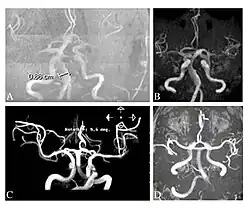

Die Time-of-Flight-Magnetresonanzangiographien von vier Morbus-Fabry-Patienten zeigen erweiterte (ekstatische) Blutgefäße (Dolichoektasien der vertebrobasilären Zirkulation).